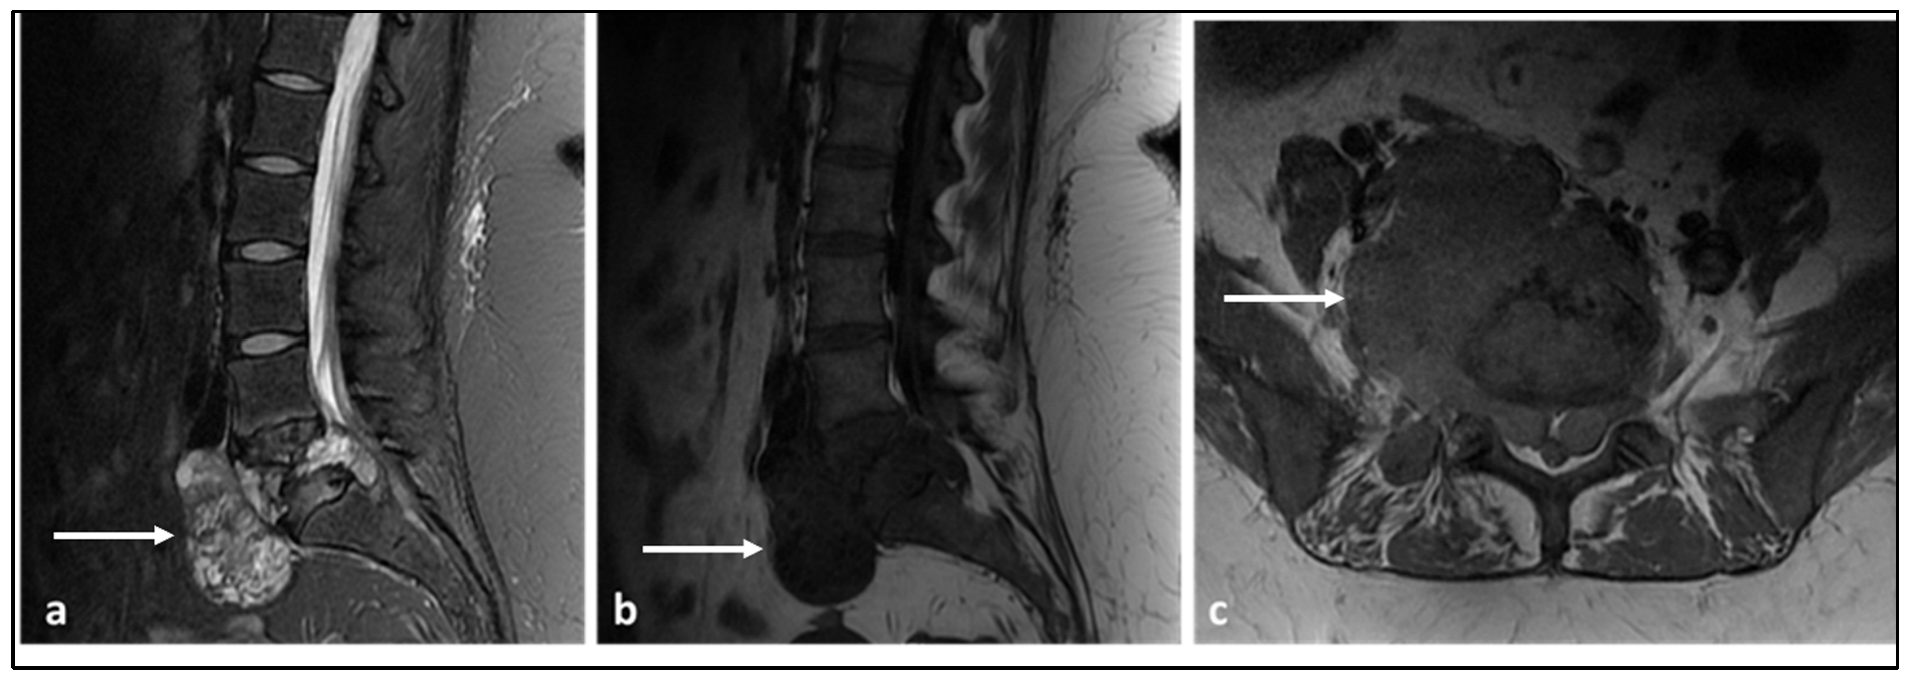

3.4. Chordoma

| Chordoma | Low attenuation lytic lesion. | Loculated high T2 signal mass, usually with extra-osseous soft tissue component. High T1 signal due to haemorrhagic and calcified components. |